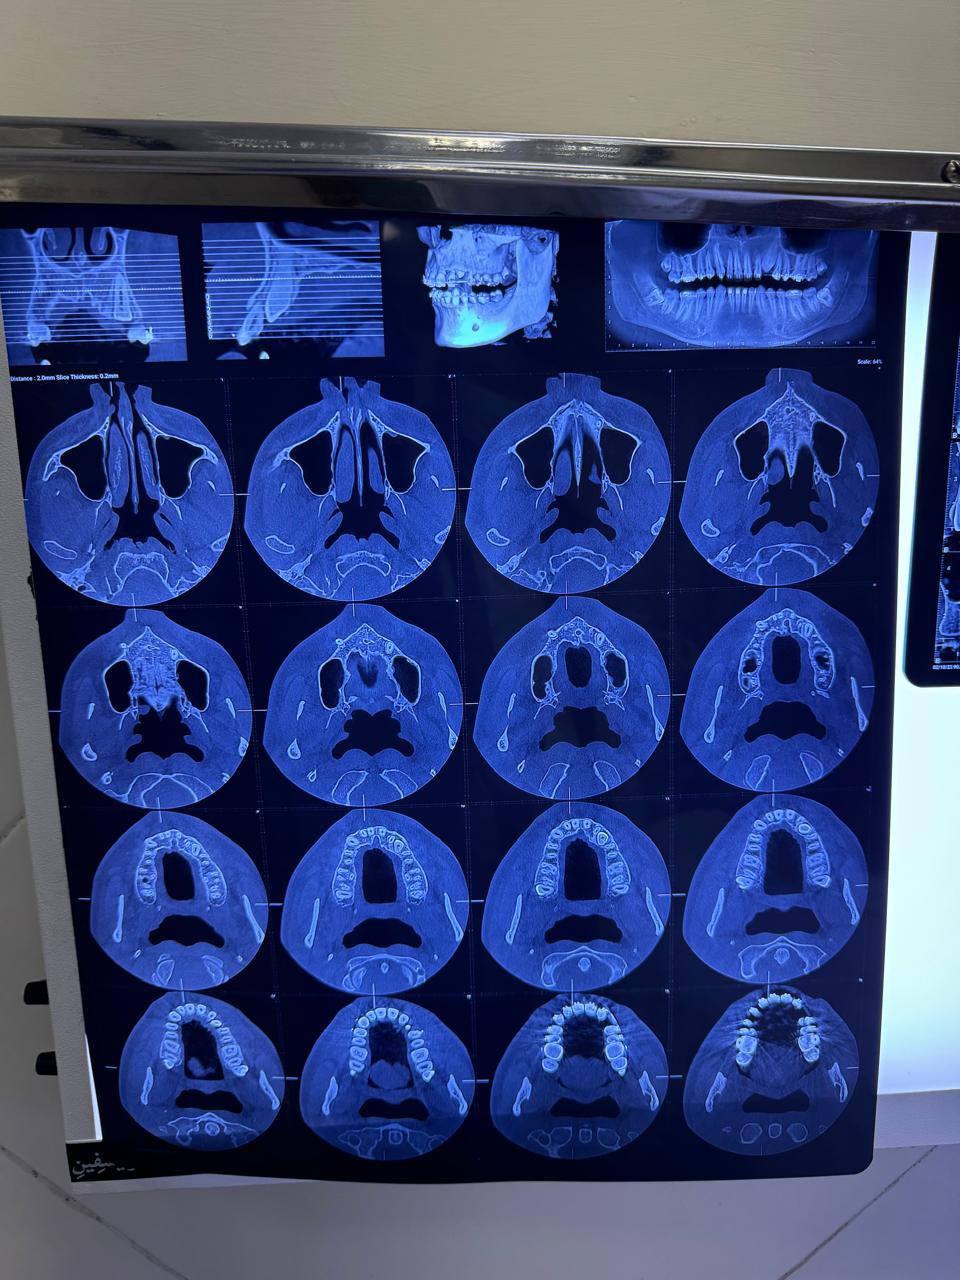

CT scan evaluation for accurate diagnosis and treatment planning of dental cases.

CT scan evaluation for accurate diagnosis and treatment planning of dental cases.